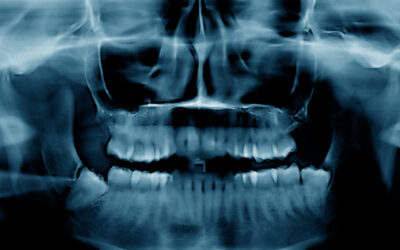

Is Bone Loss Reversible? What Patients Should Know About Modern Regenerative Dentistry

Bone loss in the jaw often happens quietly. Many patients don’t realize it has begun until a tooth...

The Role of Bone Grafting in Preserving Your Jaw After Tooth Loss

When a tooth is lost or extracted, the changes beneath the surface aren’t always...